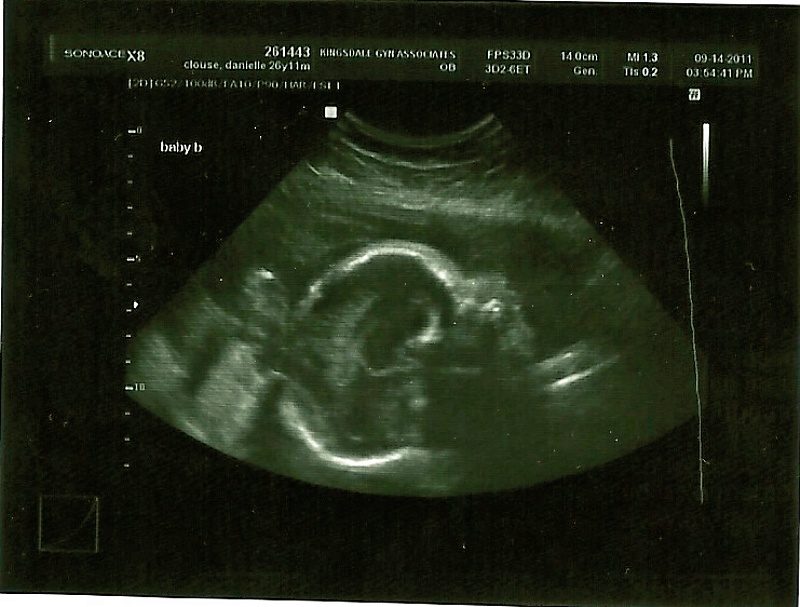

So, just to give a short update, last week I had my 28 week appointment where we had an ultrasound and 3D ultrasound done. The babies looked great during the ultrasound, their estimate weight was 1 lb. 15oz. and 2 lbs. 5 oz., so one baby is just a little bigger than the other. Baby A was head down and kind of tucked down underneath Baby B who is head up/transverse. I can definitely tell Baby B has a lot more room to move around too as he likes to kick a lot and push against the front of my belly a lot! Their measurements looked good in the ultrasound and when we tried to do a 3-D ultrasound we were not so successful. We did get one or two good pictures of Baby B (See below) where he looks like he is smiling, however, we decided Baby A is more like Tim because he was being camera-shy and facing my spine so we did not get any 3D pics of him and only a few regular ultrasound pictures. Oh, well, they both seem to be doing great, so that’s all that matters :).